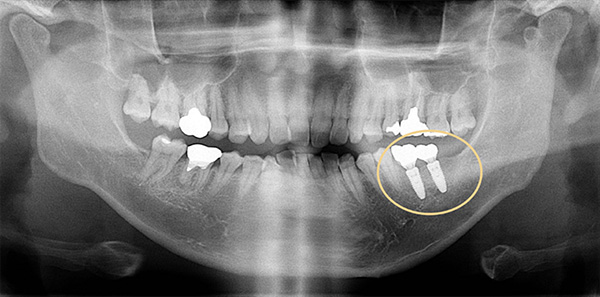

初診時:2015年 65才 女性. 右下3本(小臼歯2本、大臼歯1本)欠損

ワックスで作製した歯の完成形とCTからインプラントの3D設計を行う

正確な事前設計により、手術はスムーズかつ安全に行うことができます。

(サージカルテンプレート)